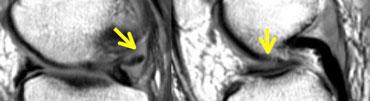

TRÁI: hình dạng bất thường của sừng sau. Một phần bị khuyết. PHẢI: mảnh di lệch trong hố liên lồi cầu.

Rách dọc (2)

Rách hình quai xô (Bucket handle tear)

là rách dọc có di lệch.

TRÁI: sụn chêm có hình dạng bất thường và có mảnh di lệch. PHẢI: Ba cấu trúc trong hố liên lồi cầu: dây chằng chéo sau (1), dây chằng chéo trước (2) và mảnh di lệch (3).

Trên ảnh mặt phẳng coronal, rách hình quai xô dễ nhận biết hơn.

Bình thường, trong hố liên lồi cầu chỉ có hai cấu trúc: dây chằng chéo trước và dây chằng chéo sau.

Bất kỳ cấu trúc nào khác trong hố liên lồi cầu đều là bất thường, và mảnh sụn chêm di lệch là khả năng có thể xảy ra nhất.